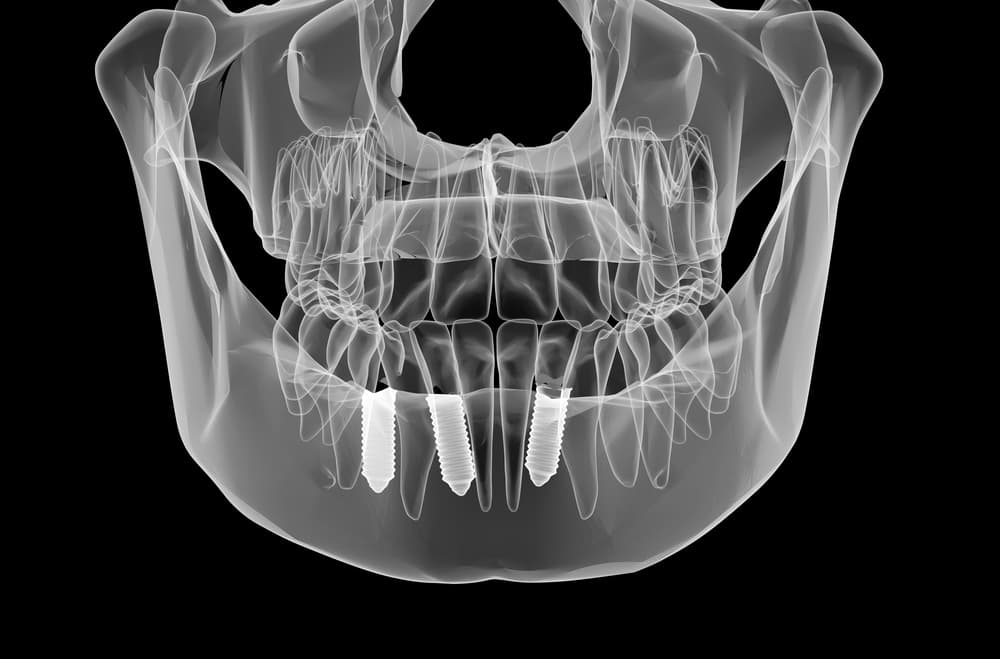

Three-dimensional imaging technology that provides complete views of dental structures from multiple angles, enabling precise treatment planning for implants, orthodontics, and surgical procedures.